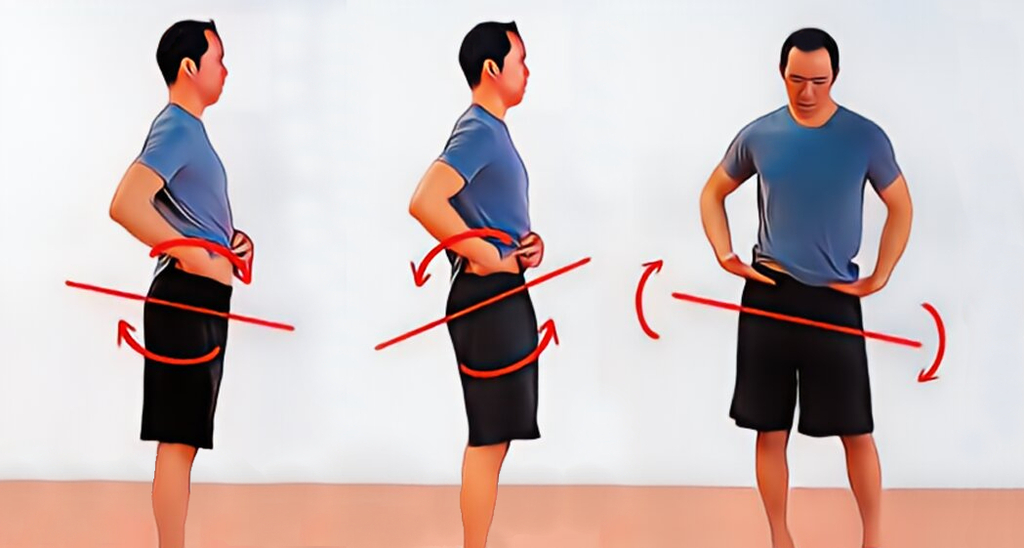

چرخش لگن یا روتیشن لگن به وضعیتی گفته می شود که یک سمت لگن نسبت به سمت دیگر به جلو یا عقب می چرخد و باعث عدم تقارن می شود. تشخیص این وضعیت بدون معاینه تخصصی کمی دشوار است، اما نشانه ها و تست های ساده ای وجود دارد که می توانند هشدار دهند. افراد معمولا با درد مبهم کمر، احساس کشیدگی در باسن یا اختلاف ارتفاع ظاهری پاها به این مشکل پی می برند.

یکی از روش های ساده تشخیص مشاهده ای است: فرد مقابل آینه ایستاده و یک متخصص یا حتی خود فرد ارتفاع خار خاصره قدامی و خلفی دو سمت لگن را بررسی می کند. همچنین نشستن یا ایستادن نامتقارن، کشیدگی یک طرفه لباس یا کفش ساییده شده بیشتر روی یک سمت نیز می تواند علامت چرخش لگن باشد. در فیزیوتراپی لگن، تست های تخصصی مانند تست لیفت پا، تست انعطاف عضلات ران و لمس دقیق مفصل ساکروایلیاک برای تشخیص نوع و شدت چرخش لگن استفاده می شود.

تمرینات و حرکات اصلاحی لگن نامتقارن

تمرینات اصلاحی بخش اصلی درمان انحراف لگن هستند. این تمرینات با هدف ایجاد تعادل بین عضلات قدامی و خلفی و همچنین عضلات دو سمت لگن طراحی می شوند. انجام منظم و صحیح آن ها تحت نظر متخصص اهمیت زیادی دارد.

حرکات کششی برای عضلات کوتاه و تمرینات تقویتی برای عضلات ضعیف تجویز می شود. در برخی موارد تمرینات تعادلی و کنترل مرکزی نیز به برنامه اضافه می گردد تا ثبات لگن در فعالیت های روزمره افزایش یابد.